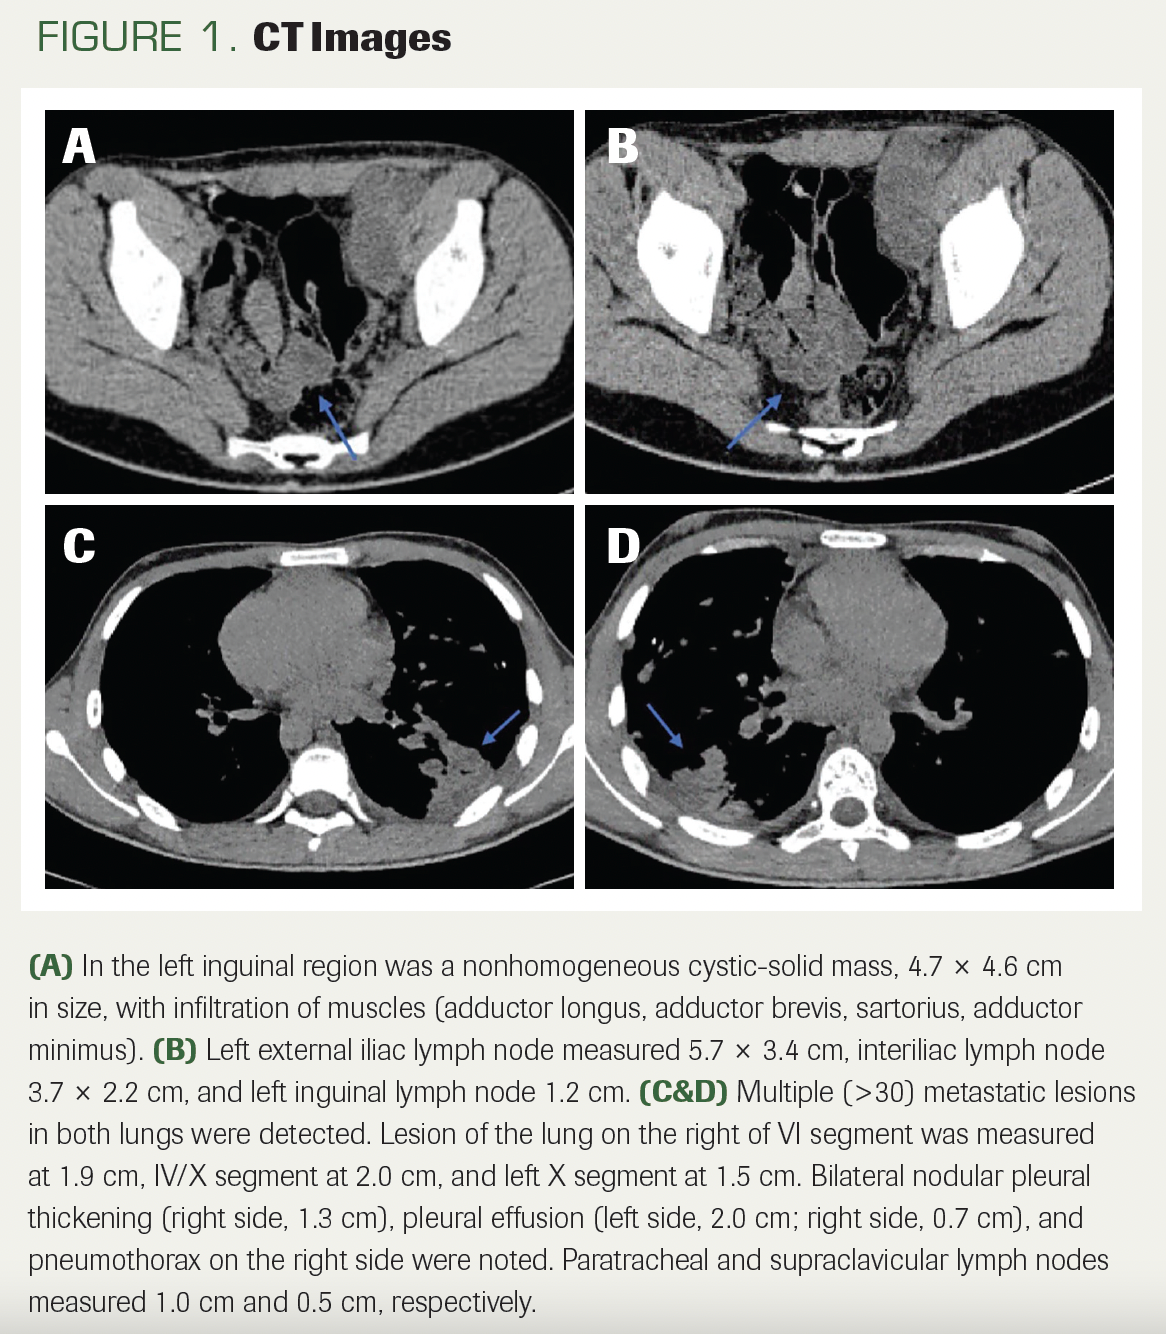

A 16-year-old boy presented with cough and dyspnea that had lasted for 1 month. He had no prior medical history, was a nonsmoker, and did not consume alcohol. Diagnostic work-up, including a CT scan, was performed. Imaging revealed an enlarged 4.6-cm inguinal lymph node, forming a very large, nonhomogeneous cystic mass measuring 15.7 cm, infiltrating several muscles: the adductor longus, adductor brevis, sartorius, and adductor minimus (Figure 1A, B). Multiple metastatic lesions in both lungs (measuring between 0.6 and 2.5 cm each) and right pleural effusion were detected (Figure 1C, D). Biopsy of the lymph node with further histology and immunohistochemistry (IHC) were performed. The tumor was described to have pleomorphic spindle malignant cells, between which there were rhabdoid cells (Figure 2). IHC stains were positive for S100, SMA, SOX10, and vimentin, and desmin was positive in rhabdomyosarcomatous elements; the loss of H3K27me3 expression in 30% of tumor cells was observed (Figure 3). The Ki67 stain demonstrated proliferative activity of 45% to 50% (Figure 3). Based on the histological and IHC examinations, malignant triton tumor (MTT) was diagnosed.